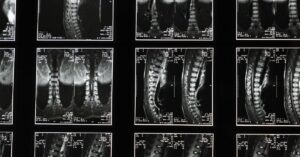

Suffering from lower back pain and discomfort? You might be facing challenges with a herniated disc. In Short: Herniated disc struggles causing you pain and